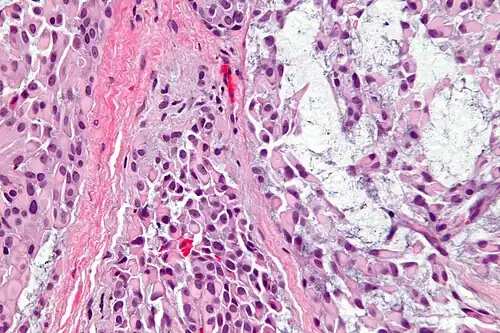

Histologicamente, é caracterizado por ser predominantemente (>95%) composto por células mioepiteliais, sejam elas de características fusiforme, epitelioide, plasmocitoide, claras ou oncocíticas.[1][5] São bem delimitados ou até mesmo encapsulados, e o estroma tumoral, quando presente, pode ser fibroso, hialinizado, mixoide ou mucinoso, raramente tendo aspecto lipomatoso.[1] A arquitetura tecidual pode ser dividida em algumas formas: sólida; mixoide; reticular (ou canalicular); ou uma mistura de mais de uma forma, sem diferenciação ductal.[1]

Uma variante rara é o mioepitelioma mucinoso, que contém mucina intracelular e pode se assemelhar ao carcinoma de células em anel de sinete, e deve ser diferenciado por marcadores imuno-histoquímicos do carcinoma secretório.[1][6]